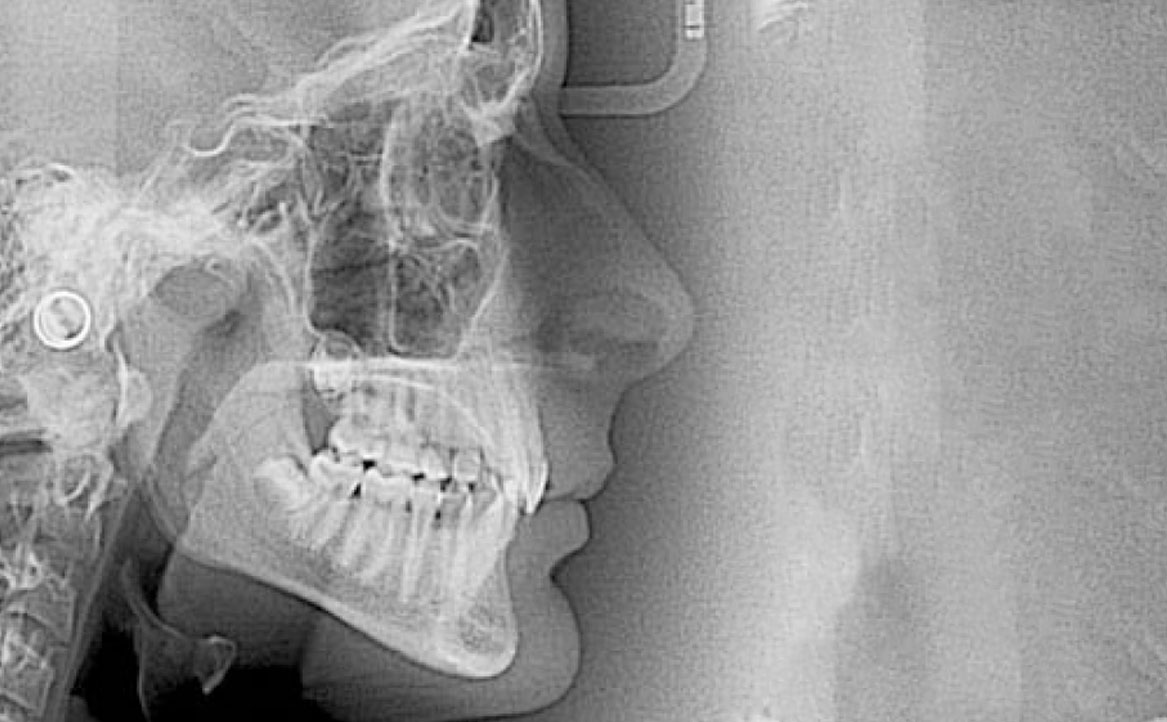

In primo luogo, sono stati prescritti entrambi gli esami radiografici ortodontici: OPT e teleradiografia latero-laterale del cranio (fig. 2a-b). Successivamente, in accordo con il genitore, è stata concordata una terapia ortodontica in due tempi. L’inizio della terapia è stato effettuato con Carriere Motion ed elastici di classe II, con l’obiettivo di migliorare la classe molare (fig. 2c-e).